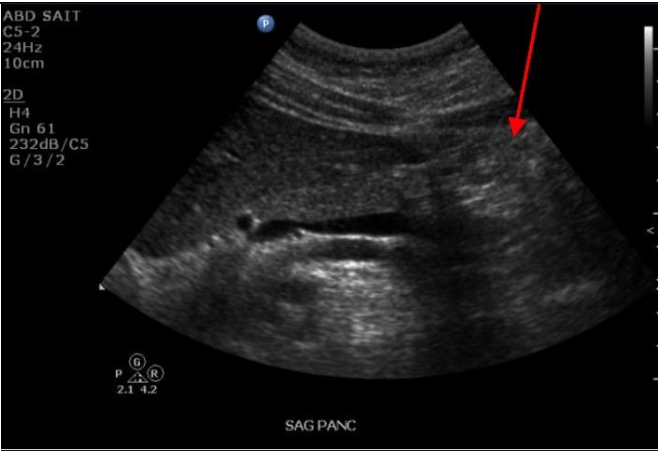

Q

Label the red arrow and the stars Counaud’s liver segment

Red: Aorta

Star: Couinaud segment 2